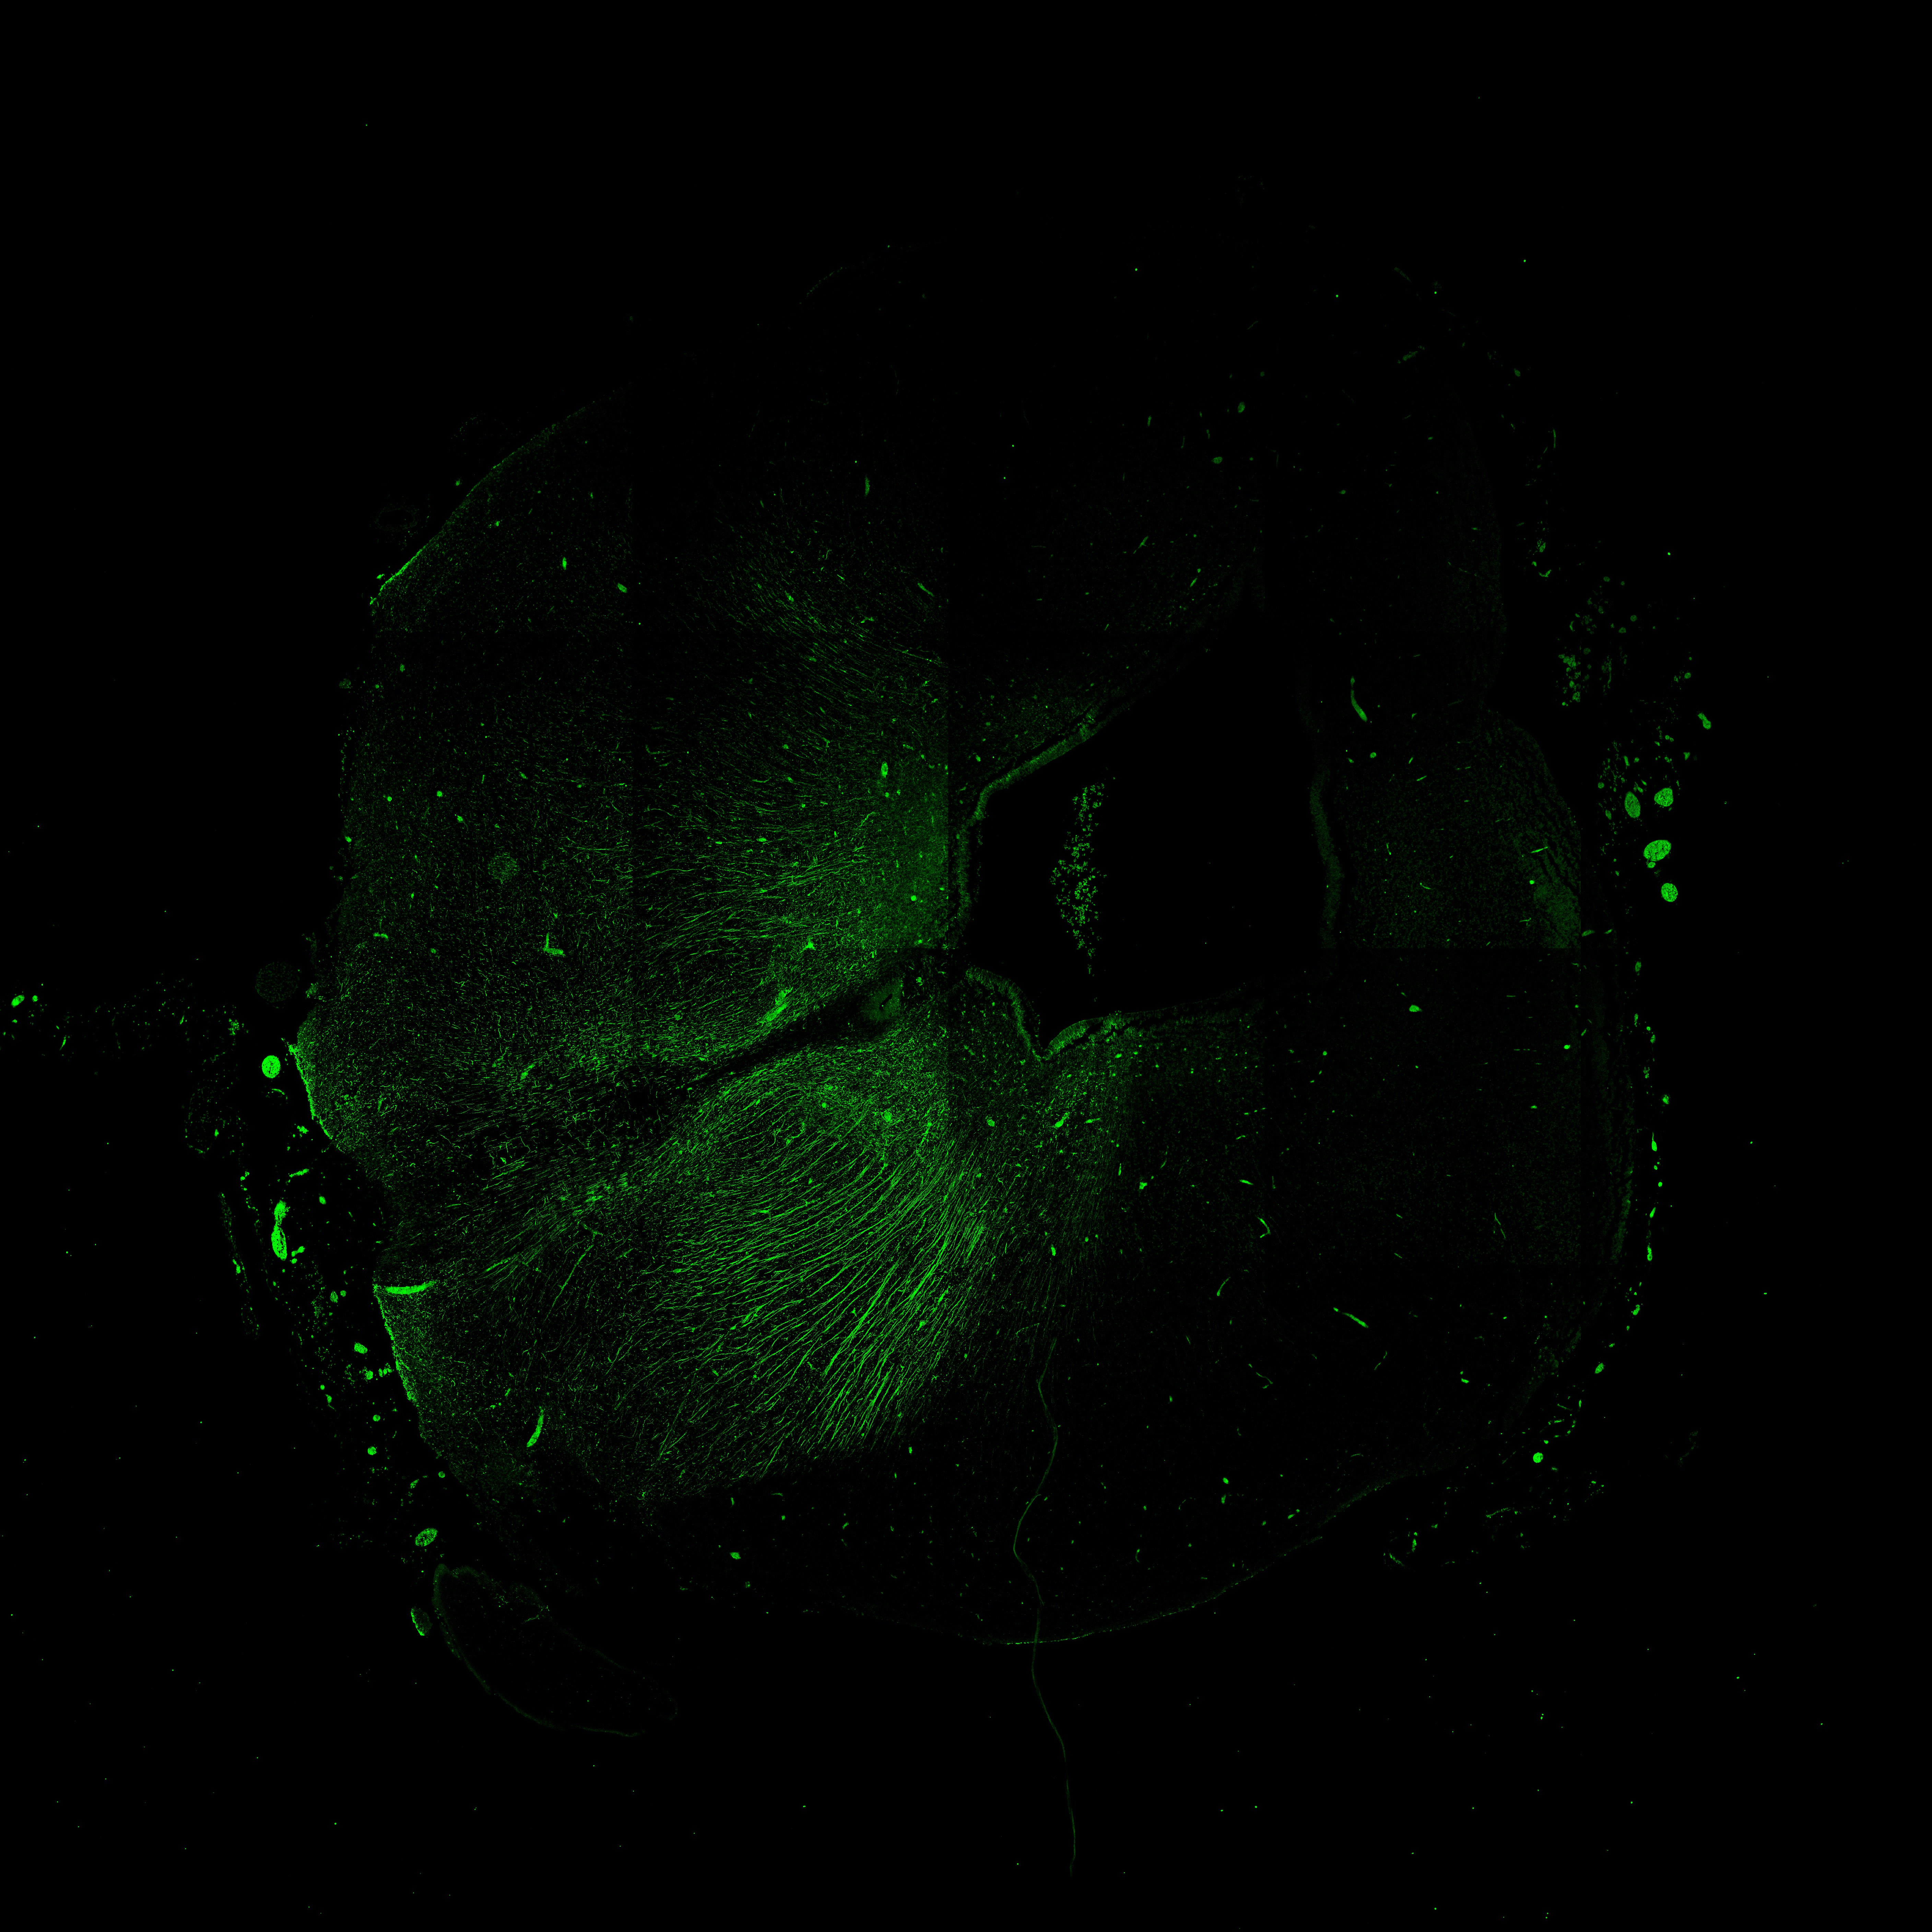

Merged

11PCW human midbrain